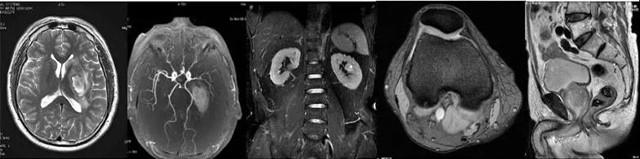

临床应用中,磁共振成像在脑、脊髓、乳腺、椎间盘、骨及软组织、盆腔等组织器官检查中具有不可取代的优势。

以下图为例,从左到右,分别是头(左一、左二)、体部、膝关节、盆腔的磁共振成像。